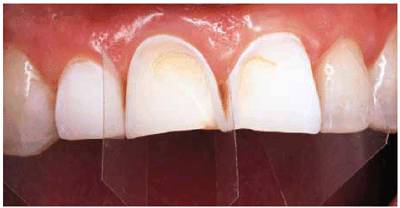

A 28-year-old woman had a severe bulimic condition over the course of many

years (Figures 17-16A 17-16B, and 17-16C). However, she underwent successful

treatment and desired to restore her smile. Since so much tooth structure had

been eroded, it was necessary to place provisional restorations followed by

crown lengthening (Figure 17-16D) and eventual replacement with the

final ceramic-metal restorations (Figures 17-16E 17-16F, and 17-16G

Figure 17-16A: This 28-year-old woman had a history of bulimia. After several years of therapy, she wanted to correct the damage caused by the bulimic condition. Note the severe occlusal erosion.

Figure 17-16B: The labial erosion seen here also contributed to the discoloration that bothered the patient.

Figure 17-16C: This before picture shows the severe labial erosion present on the posterior teeth.

Figure 17-16D: Crown lengthening and build-ups with composite resin were necessary before making the impressions for the final restorations.

Figure 17-16E: The final splinted restorations were constructed using ceramic-metal.

Figure 17-16F: The five splinted crowns restored this attractive lady's smile. Note how light a shade the patient selected.

Figure 17-16G: The new, improved shapes and shade helped to accomplish the smile desired by the patient.